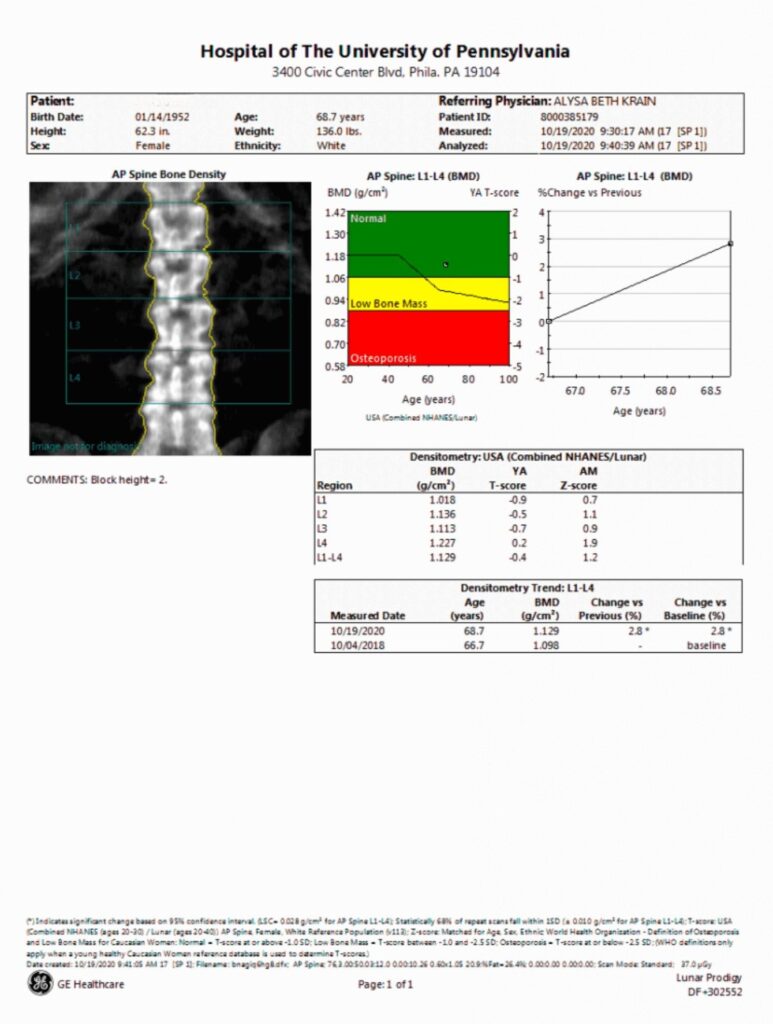

DEXA Scan

img01

Prodigy DXA systems help enhance your patient care and practice workflow with the following benefits:

• Bone Mineral Density (BMD) assessment to help with diagnosing osteoporosis

• Optional Integrated Trabecular Bone Score (TBS), Advanced Hip Assessment, FRAX and other tools can aid in assessing borderline cases

• Measurement of lean and fat-tissue mass, including percentage of fat, for body composition assessment and to help with understanding metabolic health risk

• Streamlined patient care with applications for faster scanning and less dose

• Improved practice workflow with customizable and easy-to-use reporting